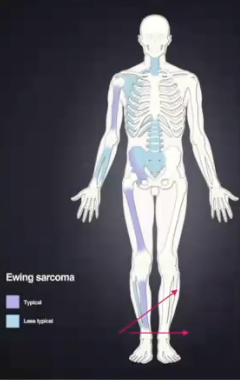

What is ewing sarcoma?

A primary malignant tumor of bone, it is highly lethal and known to metastasize (it is the 3rd most common osseous neoplasm)

What gender does ewing sarcoma affect the most?

White male, 80% less than 20 years old

Where would you find ewing sarcoma?

Long bones, jaws are only involved 2% mand > max

What are some clinical features of ewing sarcoma?

Intermittent pain

Swelling

Loosening of teeth

What are some radiographic features of ewing sarcoma?

Irregular defined borders (moth eaten)

Onion skin periosteal reaction like “Garre’s osteomyelitis”

Sunray appearance “like osteosarcoma”

What is the treatment for ewing sarcoma?

Combined surgery, chemo, and radiation